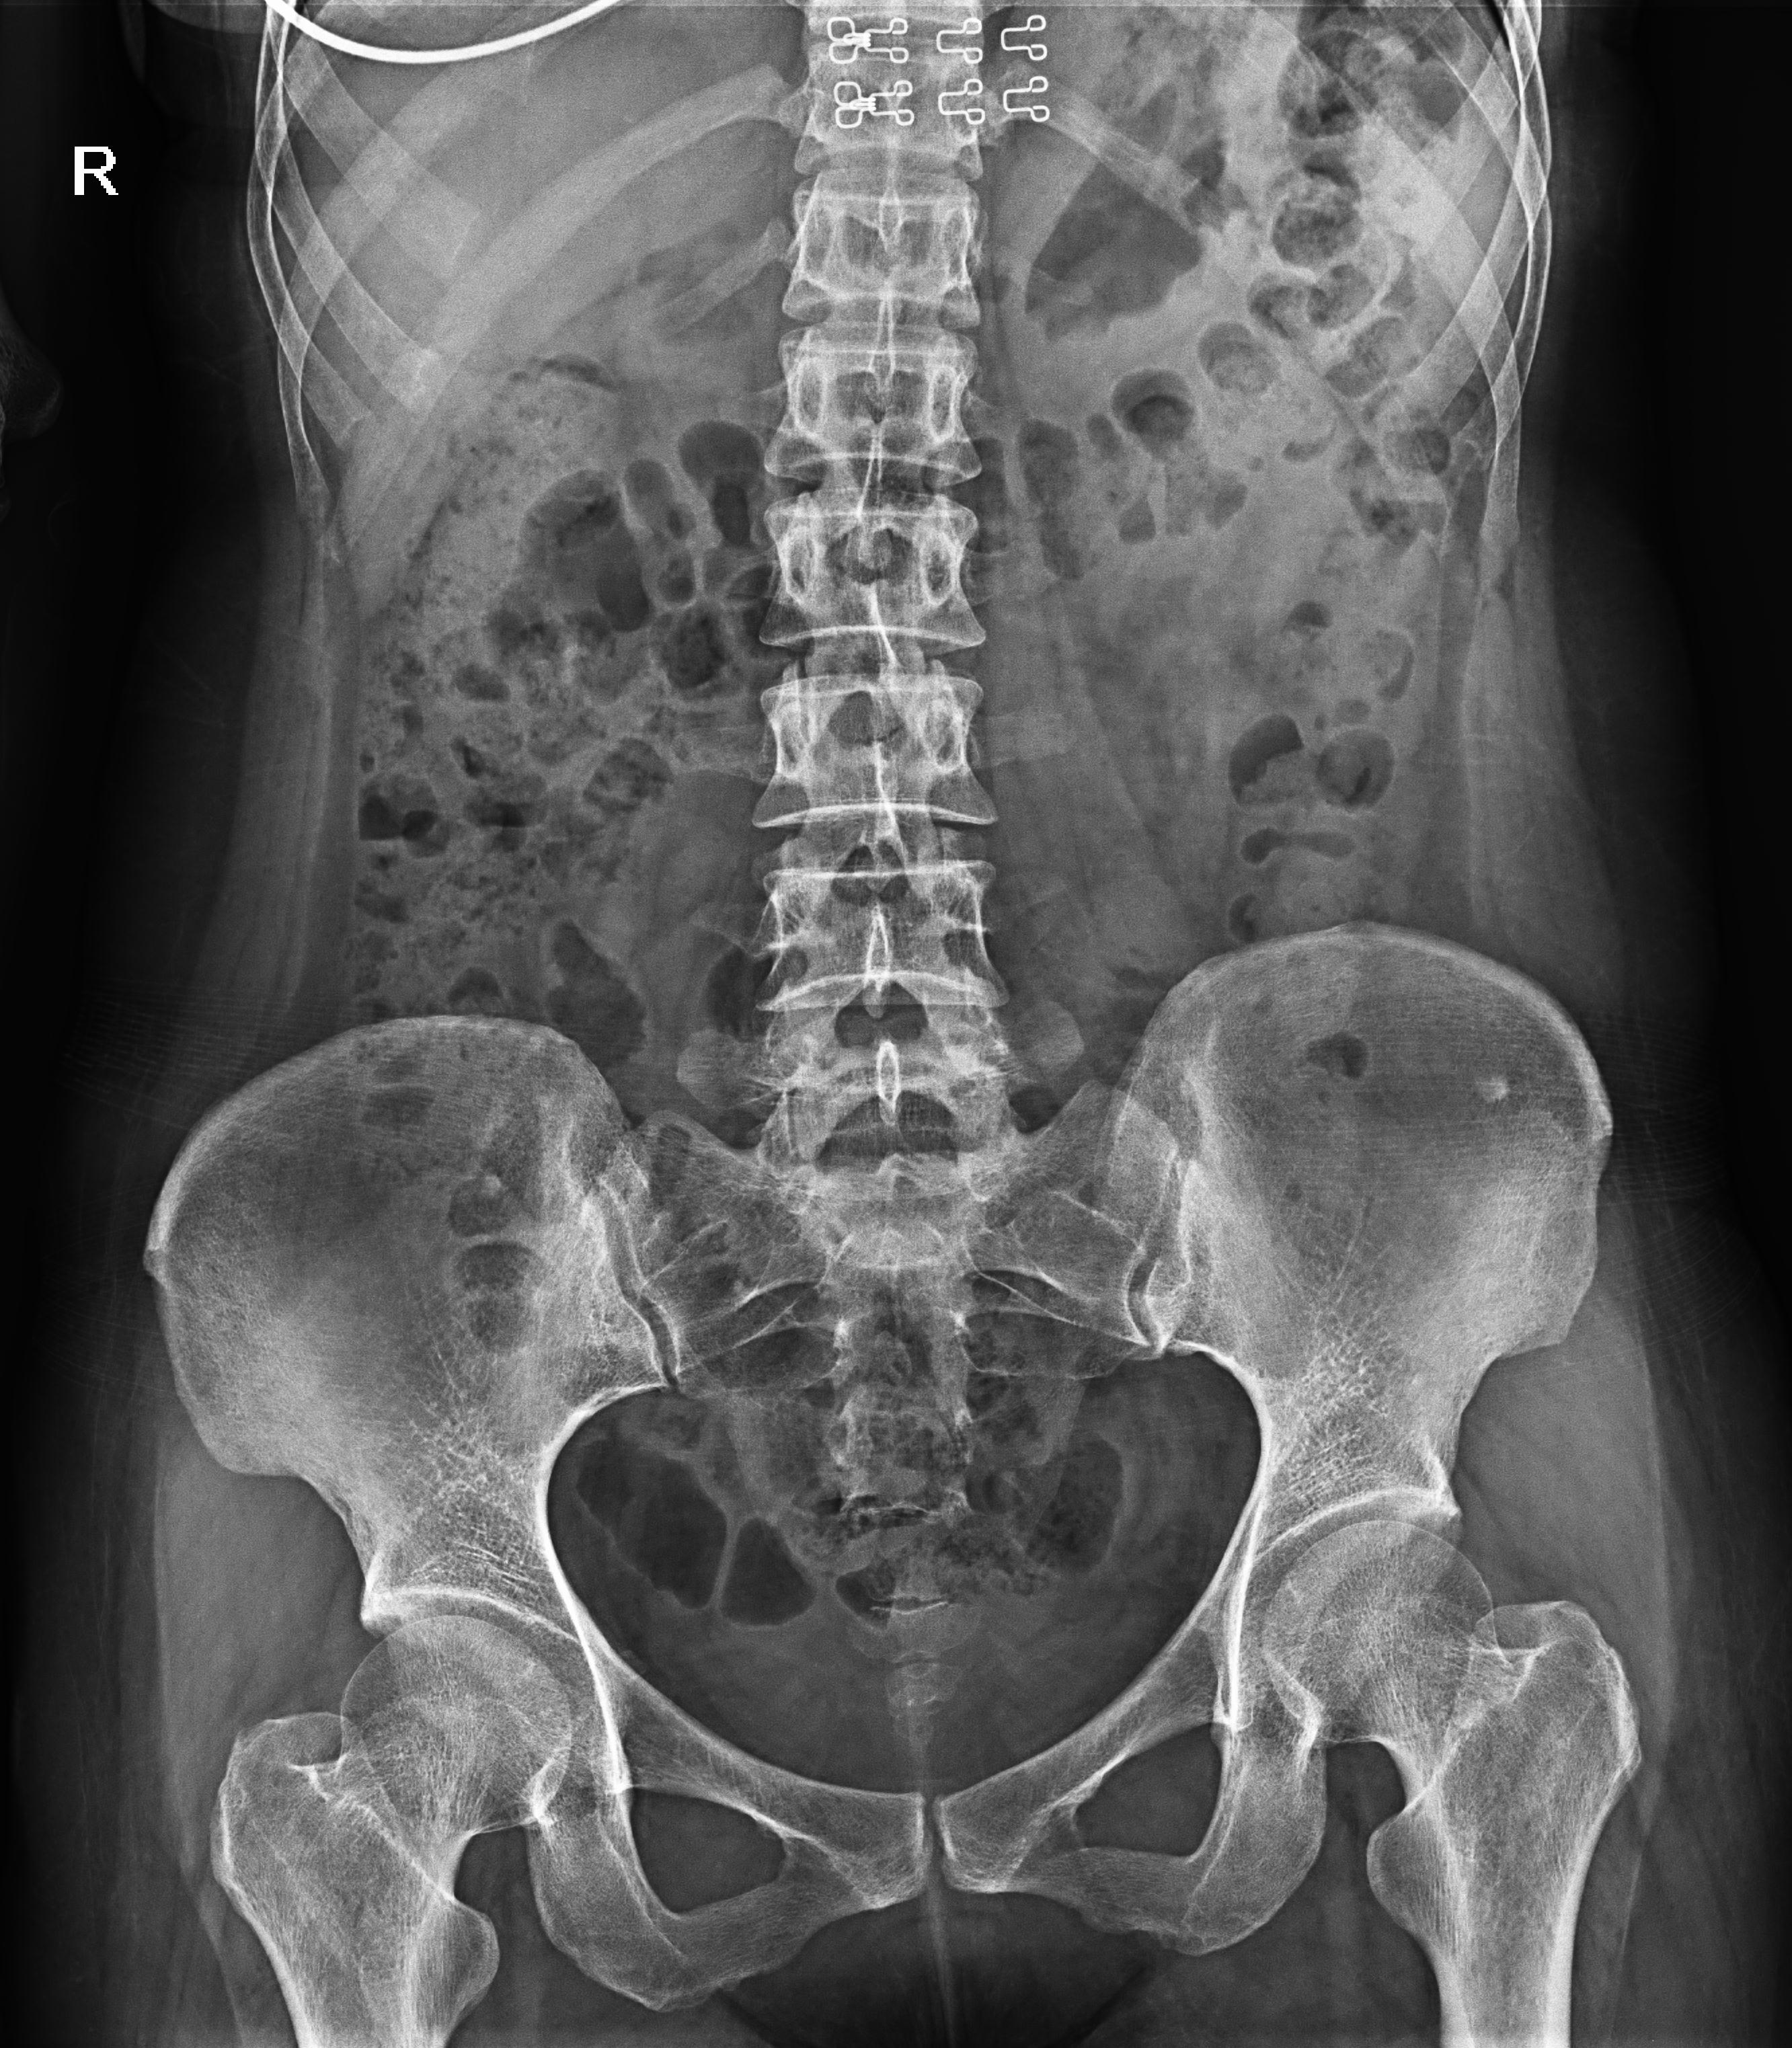

普利德醫(yī)療自主研發(fā)的新一代數(shù)字化X線透視攝影系統(tǒng),可應(yīng)用于DR攝影、數(shù)字透視、數(shù)字造影以及可視化精準(zhǔn)DR拍片等多種臨床X線檢查領(lǐng)域。

● 17*17英寸的超高清像素動(dòng)態(tài)平板探測(cè)器,更大的視野范圍,無(wú)需移動(dòng)即可觀察整個(gè)動(dòng)態(tài)過(guò)程,避免拖尾、噪聲對(duì)圖像的影響;

● 高效動(dòng)態(tài)平板技術(shù),圖像不會(huì)有幾何畸變,提供高分辨率和精確的圖像,為醫(yī)生臨床診斷提供精準(zhǔn)依據(jù);

● 最高幀速可達(dá)30幀/秒,動(dòng)態(tài)采集清晰流暢,避免漏診、誤診情況的發(fā)生;

● 在可視過(guò)程或回放過(guò)程中,如發(fā)現(xiàn)疑似病灶,可進(jìn)行毫秒級(jí)高清點(diǎn)片,隨時(shí)抓取單幀圖像,精準(zhǔn)捕抓病灶。